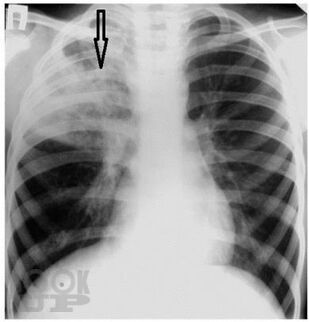

Излагается современная информация по классификации пневмонии у детей, ее эпидемиологии, этиологии, клинических особенностях в зависимости от этиологических и анатомо-физиологических факторов и фоновых заболеваний. Значительная часть пособия посвящена диагностике, принципам современной антибактериальной терапии с последних достижений в педиатрии.